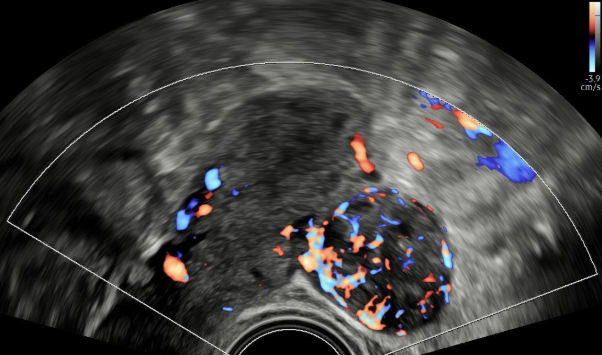

Ultrazvuk myomu dělohy rostoucího pod děložní sliznicí.Děložní myomy jsou nezhoubné nádory, které vyrůstají ve svalové stěně dělohy. Jsou velmi časté a mohou se objevit u žen v jakémkoli věku. Zatímco některé ženy o nich ani nevědí, jiné mohou trpět bolestmi, silným menstruačním krvácením, tlakem v podbřišku nebo dokonce problémy s otěhotněním. Velikost a umístění myomů hrají klíčovou roli v tom, jak moc ovlivňují každodenní život ženy.

Myom dělohy rostoucí do dutiny břišní.